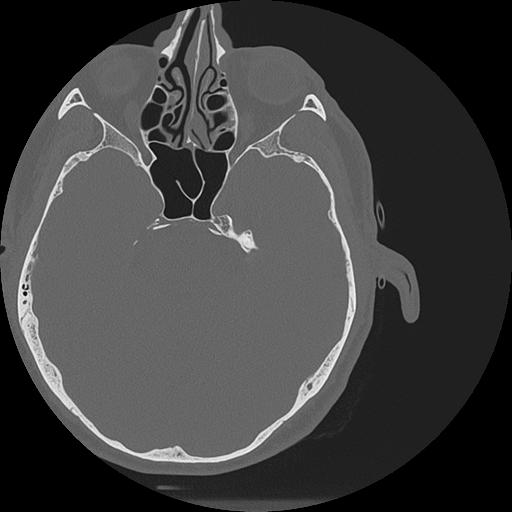

7 HUESO,,Vol,0.5,HUESO,,